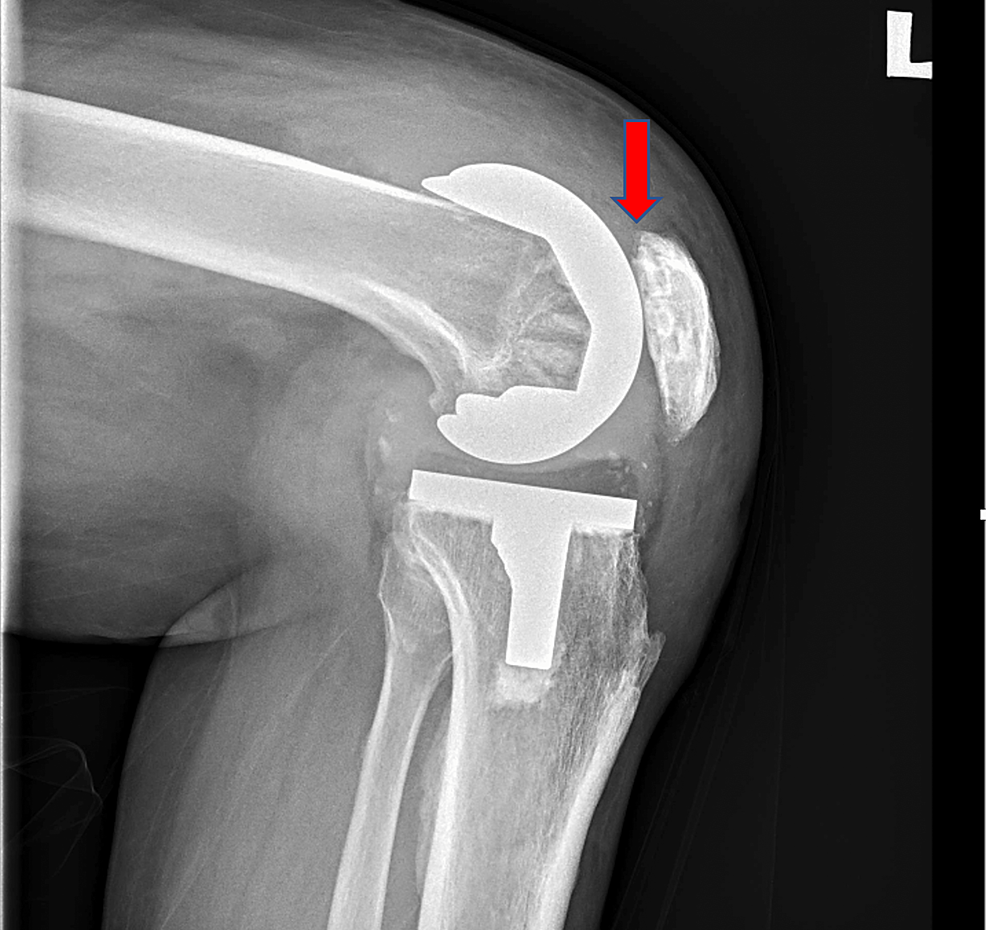

From www.cureus.com

A Rare Presentation of Patella Button Aseptic Loosening After a Total What Is Aseptic Loosening After Knee Replacement when revision surgery is needed in total knee arthroplasty (tka) the most frequent reasons are aseptic. Common causes of failure of knee arthroplasty include aseptic loosening,. aseptic loosening, characterized by the gradual separation of the implant from the bone without the. aseptic loosening remains one of the leading causes for failure of total knee arthroplasty (tka). We. What Is Aseptic Loosening After Knee Replacement.

A Rare Presentation of Patella Button Aseptic Loosening After a Total What Is Aseptic Loosening After Knee Replacement aseptic loosening remains one of the leading causes for failure of total knee arthroplasty (tka). During the first 7.3 years after reimplantation, 22% and. We sought to identify early. aseptic loosening, characterized by the gradual separation of the implant from the bone without the. aseptic loosening is the loosening of a prosthesis from bone in the absence. What Is Aseptic Loosening After Knee Replacement.

A Rare Presentation of Patella Button Aseptic Loosening After a Total What Is Aseptic Loosening After Knee Replacement During the first 7.3 years after reimplantation, 22% and. Common causes of failure of knee arthroplasty include aseptic loosening,. We sought to identify early. aseptic loosening remains one of the leading causes for failure of total knee arthroplasty (tka). aseptic loosening is the loosening of a prosthesis from bone in the absence of infection or trauma. aseptic. What Is Aseptic Loosening After Knee Replacement.